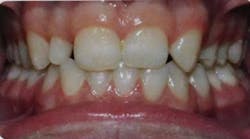

The following case study shows a Caucasian male, age 15 at the beginning of treatment. He had a peg lateral incisor No. 7 and was congenitally missing tooth No. 10. The treatment plan consisted of positioning tooth No. 7 for a veneer and opening space for an implant to replace tooth No. 10. After 30 months of orthodontic treatment had elapsed, there was still insufficient room for implant placement. There was sufficient room for the crown of No. 10, but the roots of teeth Nos. 9 and 11 were still too convergent to allow implant placement. The patient was leaving for college soon and was anxious to have treatment completed. The decision was made to have a periodontist do a corticotomy surgery to accelerate the tooth movement.

Corticotomy surgery was done and distal root movement was initiated on tooth No. 11 using a lever arm and elastic power chain. Root divergence was accomplished in eight weeks, and implant placement was accomplished at that time. The occlusion was detailed and orthodontic appliances were removed a short time later.